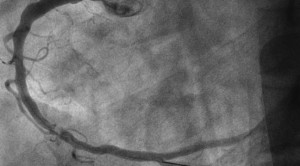

Percutaneous coronary intervention atau intervensi koroner perkutan pada sindrom koroner akut dapat dilakukan dengan pendekatan radial atau femoral. Masing-masing pendekatan ini mempunyai...(Baca Selengkapnya)